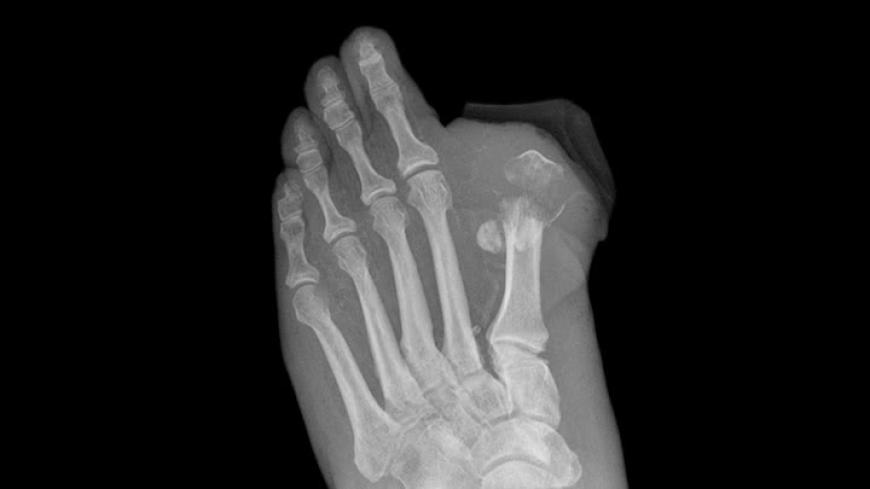

The European Medicines Agency (EMA), the European equivalent of the FDA, is reviewing a possible association between canagliflozin and amputations (mainly of the toe), which have been observed in an ongoing drug trial.

EMA started a review of canagliflozin after patients enrolled in CANVAS showed an increase in lower limb amputations. The agency says that the link between canagliflozin and lower limb amputations is not confirmed, but it is looking further into the matter.